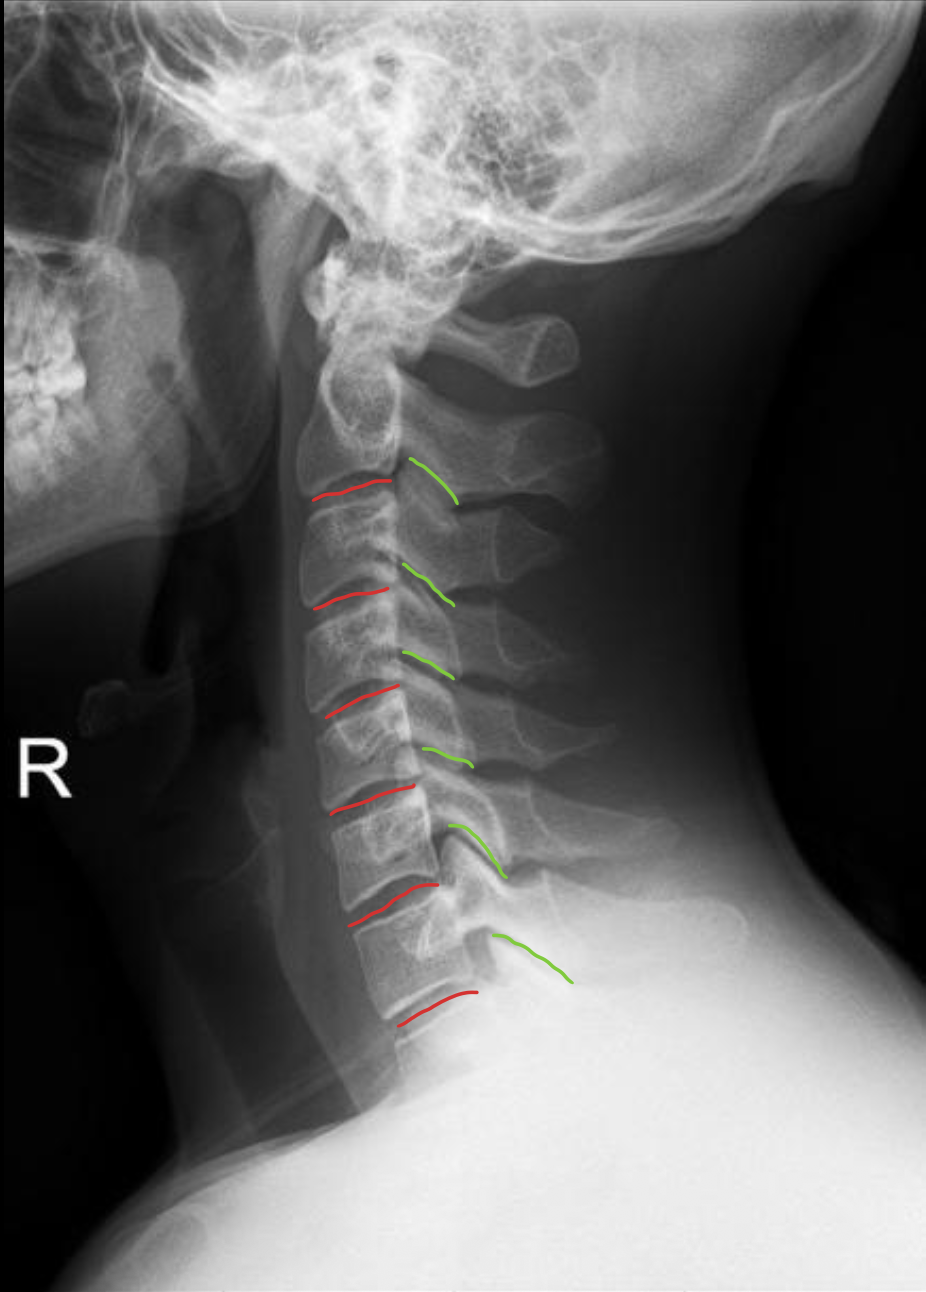

椎板棘突线(椎弓后缘线)

Spinolaminar

棘突后缘线

Posterior spinous

棘突

Spinous process

关节突关节(小关节)

Zygapophyseal

椎间盘(Intervertebral Disc)

IVD